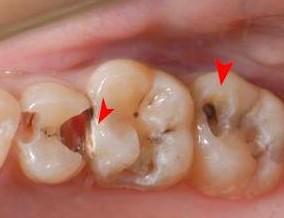

step2:中龋

当你吃糖的时候,感觉酸疼,你说:“没关系,只是一阵,一会就好了。”

牙医却说:“病菌已经抵达牙本质层了,牙齿已经有龋洞形成了,对酸甜食物较敏感,需要做修补。”

step3:深龋

主人,当你遇到冷热酸甜的时候,出现刺痛,没法咬食物,你说:“还好,可以用另外一边牙齿咬。”

牙医告诫说:“细菌攻破牙本质快接近牙髓了,牙齿有较深的龋洞,温度刺激,化学刺激以及食物进入龋洞时均引起疼痛,此时,及时做充填治疗的话还来得及保住牙髓。”